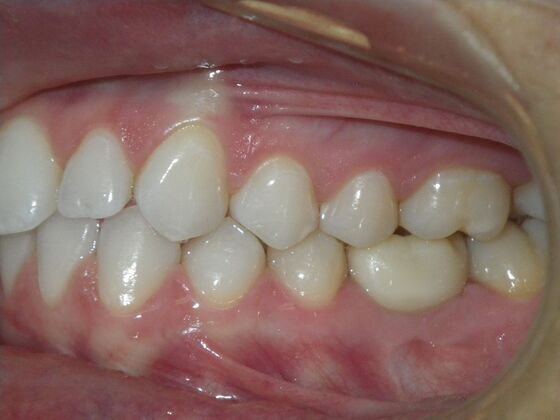

This patient was an awesome dental assistant for our practice and we were all very sad when she had to move closer to her home. She was very interested in correcting some minor spacing and rotations in her upper and lower anterior teeth and to decrease her overbite as well.Treatment took about 12 months, but we were pleased with the results and fabricated clear invisalign vivera retainers. We are still hoping one day she will return to be with us again.